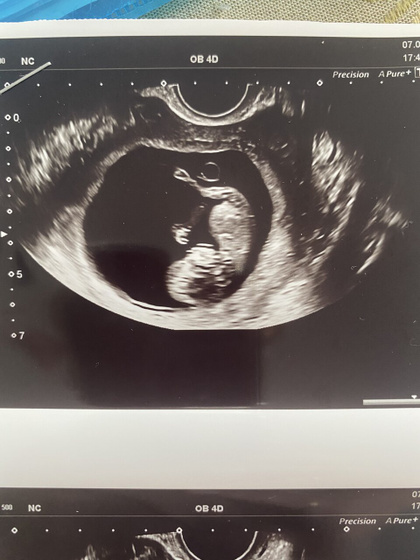

Вчера была у врача, нам сделали узи. Малышок такой большой уже стал. Как и прежде опережает развитие на 1 нед 1 день. Чсс 155 уд. Ктр 44 мм. Такой подвижный, ручками и ножками машет. Милота ?. Врач сказала, что он лежит головкой вниз. Единственное, что вызвало опасение, фраза «плацента перекрывает область внутреннего зева». Врач сказала, что плацента близко к хориону, что то такое. Кто знает, это опасно? И еще врач выписала клексан 0.4. Но я наблюдаюсь у гематолога, у Куваева, он мне не назначил клексан, тк нет показаний, гемостаз отличный, и мутации не серьезные. Вот я и думаю, надо колоть клексан или не надо?? ведь на него если подсаживаться, то до самых родов ведь?

Милота какая. Я завтра пойду, надеюсь все хорошо у нас. Мы в 8,2 делали, тоже так же написано, что перекрывает, врач вообще ничего не сказала

Хорошее какое фото. У меня по узи постоянно надо было разглядывать, чтоб понять где что ?